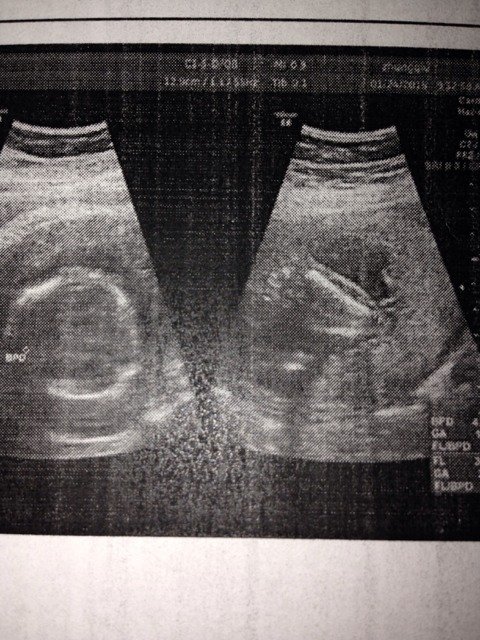

18周宝宝图 男孩儿女孩儿阿 18周宝宝图。男孩儿女孩儿阿。 点击展开 护士开花 2015-03-02 09:49 为您推荐: 其他回答 这个看不出来的 FJ 2015-03-02 10:44 看不出来,, 寶貝兒, 2015-03-02 10:26 这样是看不出来孩子的性别的,还是需要定期去医院复查的,一般是怀孕五个月左右可以检查出来的。 liuwenda1989 2015-03-02 10:05 男宝吧。。 t lo w x 2015-03-02 09:59 问,,,医生 铭哲麻麻 2015-03-02 09:54 加载更多 相关问题 怀孕37周,宝宝每分钟胎心率是150,是男孩儿还是女孩儿啊? 我家宝宝36周,前两周做了2次胎儿心电图,心电图老是在160到170上下波动,请问要不要紧,胎儿心 怀孕18周4天可以看出宝宝男女了吗 呵呵 好奇